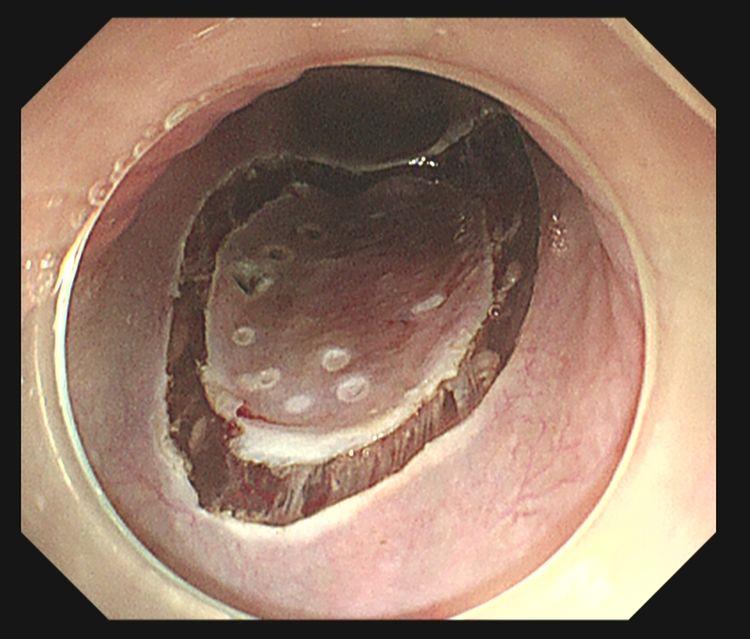

卢戈碘染示:病变区域呈不染区,粉红征阳性

术后标本卢戈碘染示:病灶完整剥离